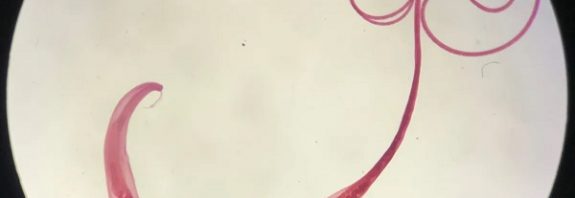

Antik Viking Kakası Gösterdi ki; Bağırsak Solucanları İnsanlığın En Yakın Arkadaşı

Antik Viking Kakası Gösterdi ki; Bağırsak Solucanları İnsanlığın En Yakın Arkadaşı Bilim insanları, 2.500 yıl önce kullanılan Viking tuvaletlerindeki dışkılardan … Antik Viking Kakası Gösterdi ki; Bağırsak Solucanları İnsanlığın En Yakın Arkadaşı okumayı sürdür